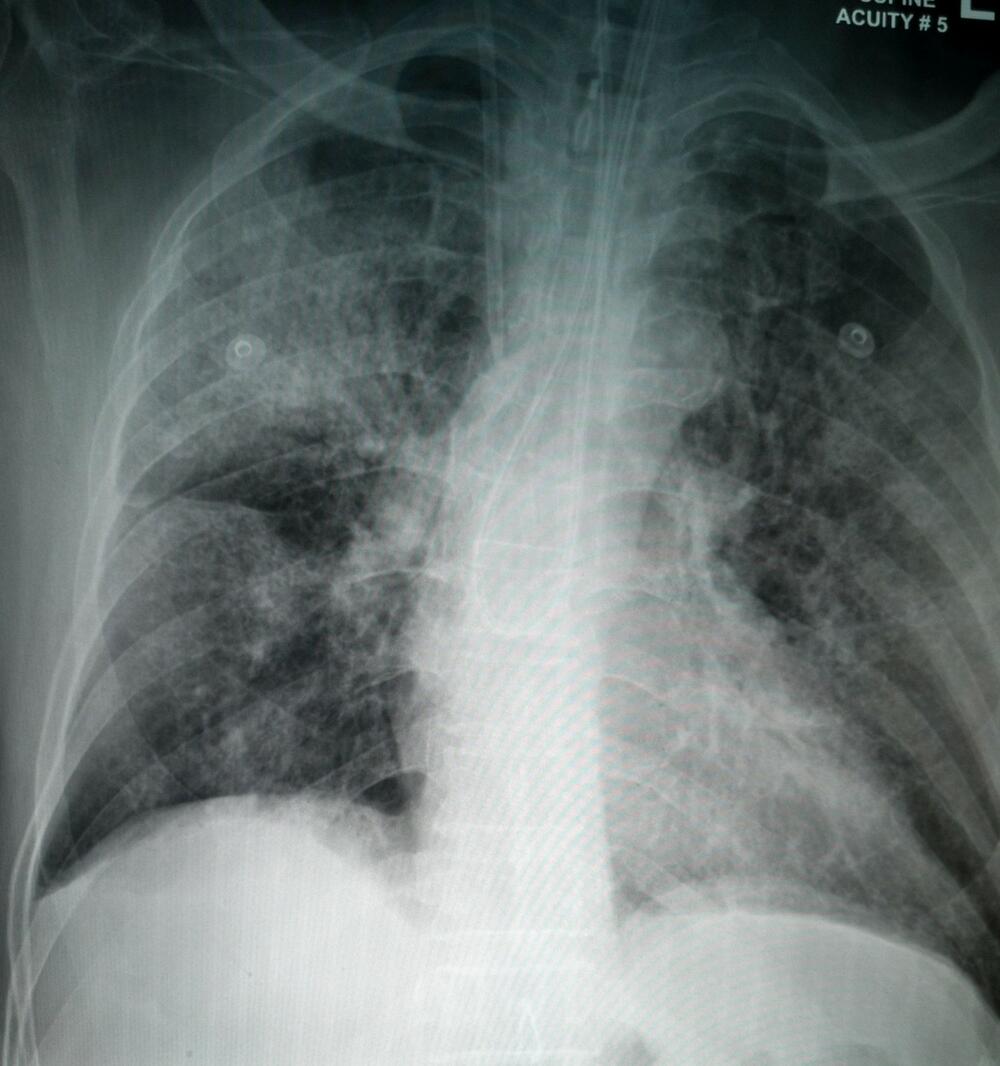

Skrining program podrazumeva detekciju karcinoma pluća pomoću niskodoznog skenera (LDCT), uz pomoć kojeg se se mogu prikazati manje tumorske senke, koje nije moguće videti uobičajenim dijagnostičkim postupcima (RTG).

Ovom metodom u Vojvodini je do sada pregledano više od 1.900 pacijenata. Kod njih 34 je otkriven karcinom pluća koji je bio asimptomatski, a kod 50 odsto njih u početnom stadijumu. Na rano otkrivanje raka pluća treba da budu obuhvaćene visokorizične grupe, u koje spadaju osobe starije od 50 godina, pušači, kao i oni koji imaju porodičnu istoriju obolevanja od raka pluća ili druge hronične plućne bolesti.